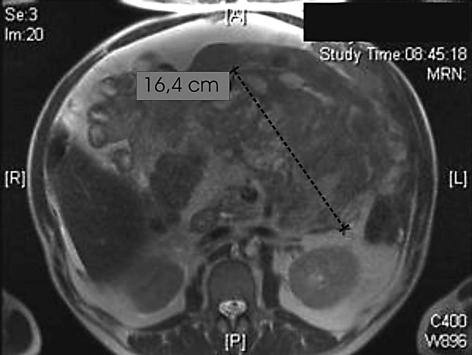

We present the case of a 64-year-old patient who presented to his primary care physician with fatigue, worsening shortness of breath, abdominal discomfort and a rapidly growing abdominal girth, although he had lost 5 kg of weight within 3 months. He had a history of untreated hypertension, compensated renal insufficiency and COPD. Despite weight loss and fatigue, the patient did not experience any other constitutional symptoms such as fever, night sweats or loss of appetite. Investigations: Physical examination, blood tests, CT scan of the abdomen, MRI scan of the abdomen, fine needle biopsy, excisional biopsy, Video Capsule Endoscopy, histology, PET scan. Diagnosis: Inflammatory myofibroblastic tumor, chylous ascites, chyloperitoneum. Management: Systemic chemotherapy, total parenteral nutrition and octreotide therapy. CONCLUSION: WE DESCRIBE THE CASE OF A PATIENT IN WHOM TWO EXTREMELY RARE PHENOMENA ARE PRESENT IN COMBINATION: the diagnosis of an inflammatory myofibroblastic tumor and chylous ascites. While the tumor could be stabilized by different regimens of chemotherapy, the chyloperitoneum was treated with parenteral nutrition and subcutaneous octreotide injections, which resulted in a significant reduction of the amount of chylous ascites drained during regular paracentesis.